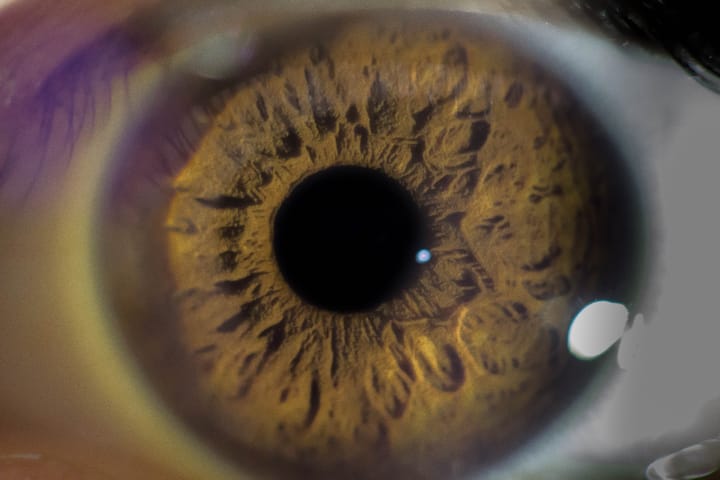

ছানি বা ইংরেজিতে যাকে বলে-Cataract, এটি হল চোখের এক ধরনের রোগ। এর রোগ দেখা দিলে প্রাথমিকভাবে চোখের লেন্স অস্বচ্ছ বা ঘোলা হতে শুরু করে, ফলে দৃষ্টিশক্তি ক্ষিণ হতে থাকে।

কী কী কারণে ছানির সমস্যা হতে পারে? বার্ধক্যজনিত কারণে (Age related cataract), শরীরের অন্য অসুখের কারণে (Cataract in systemic disease), চোখের কোন অসুখের জটিলতার ফলে (Secondary or Complicated cataract), আঘাতজনিত কারণে (Traumatic cataract)।